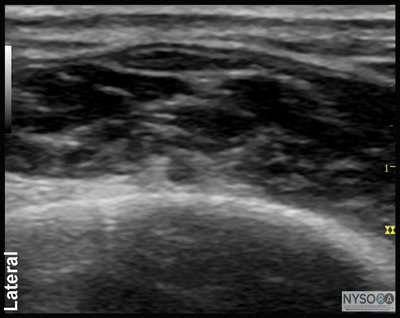

Figure 1: Block of the posterior tibial nerve using an out-of-plane technique. Essentials

![]() Figure 2: Cross-sectional anatomy of the posterior tibial nerve at the level of the ankle. Shown are posterior tibial artery (PTA) and vein (PTV) behind the medial malleolus (Med. Mall.) The posterior tibial nerve (PTN) is just posterior and superficial to the posterior tibial vessels. General Considerations Using an ultrasound-guided technique affords a practitioner the ability to reduce the volume of local anesthetic required for ankle blockade. Because the nerves involved are located relatively close to the surface, ankle blocks are easy to perform technically; however, knowledge of the anatomy of the ankle is essential to ensure success. Ultrasound Anatomy Ankle block involves anesthetizing five separate nerves: 2 deep nerves and 3 superficial nerves. The 2 deep nerves are tibial (TN) and deep peroneal nerve (DPN). The superficial nerves are superficial peroneal, sural and saphenous. All nerves except saphenous nerve are terminal branches of the sciatic nerve; saphenous nerve is a cutaneous extension of the femoral nerve. Tibial Nerve The tibial nerve is the largest of the five nerves at the ankle level and provides innervation to the heel and sole of the foot. With a linear transducer placed transversely at (or just proximal to) the level of the medial malleolus, the nerve can be seen immediately posterior to the posterior tibial artery (Figures 1, 2, and 3A and B). Color Doppler can be very useful in depicting the posterior tibial artery when it is not readily apparent. The nerve typically appears hyperechoic with dark stippling. A useful mnemonic for the relevant structures in the vicinity is Tom, Dick ANd Harry, which refers to, from anterior to posterior, the tibialis anterior tendon, flexor digitorum longus tendon, artery/nerve/ vein, and flexor hallucis longus tendon. These tendons can resemble the nerve in appearance, which can be confusing. The nerve's intimate relationship with the artery should be kept in mind to avoid misidentification.